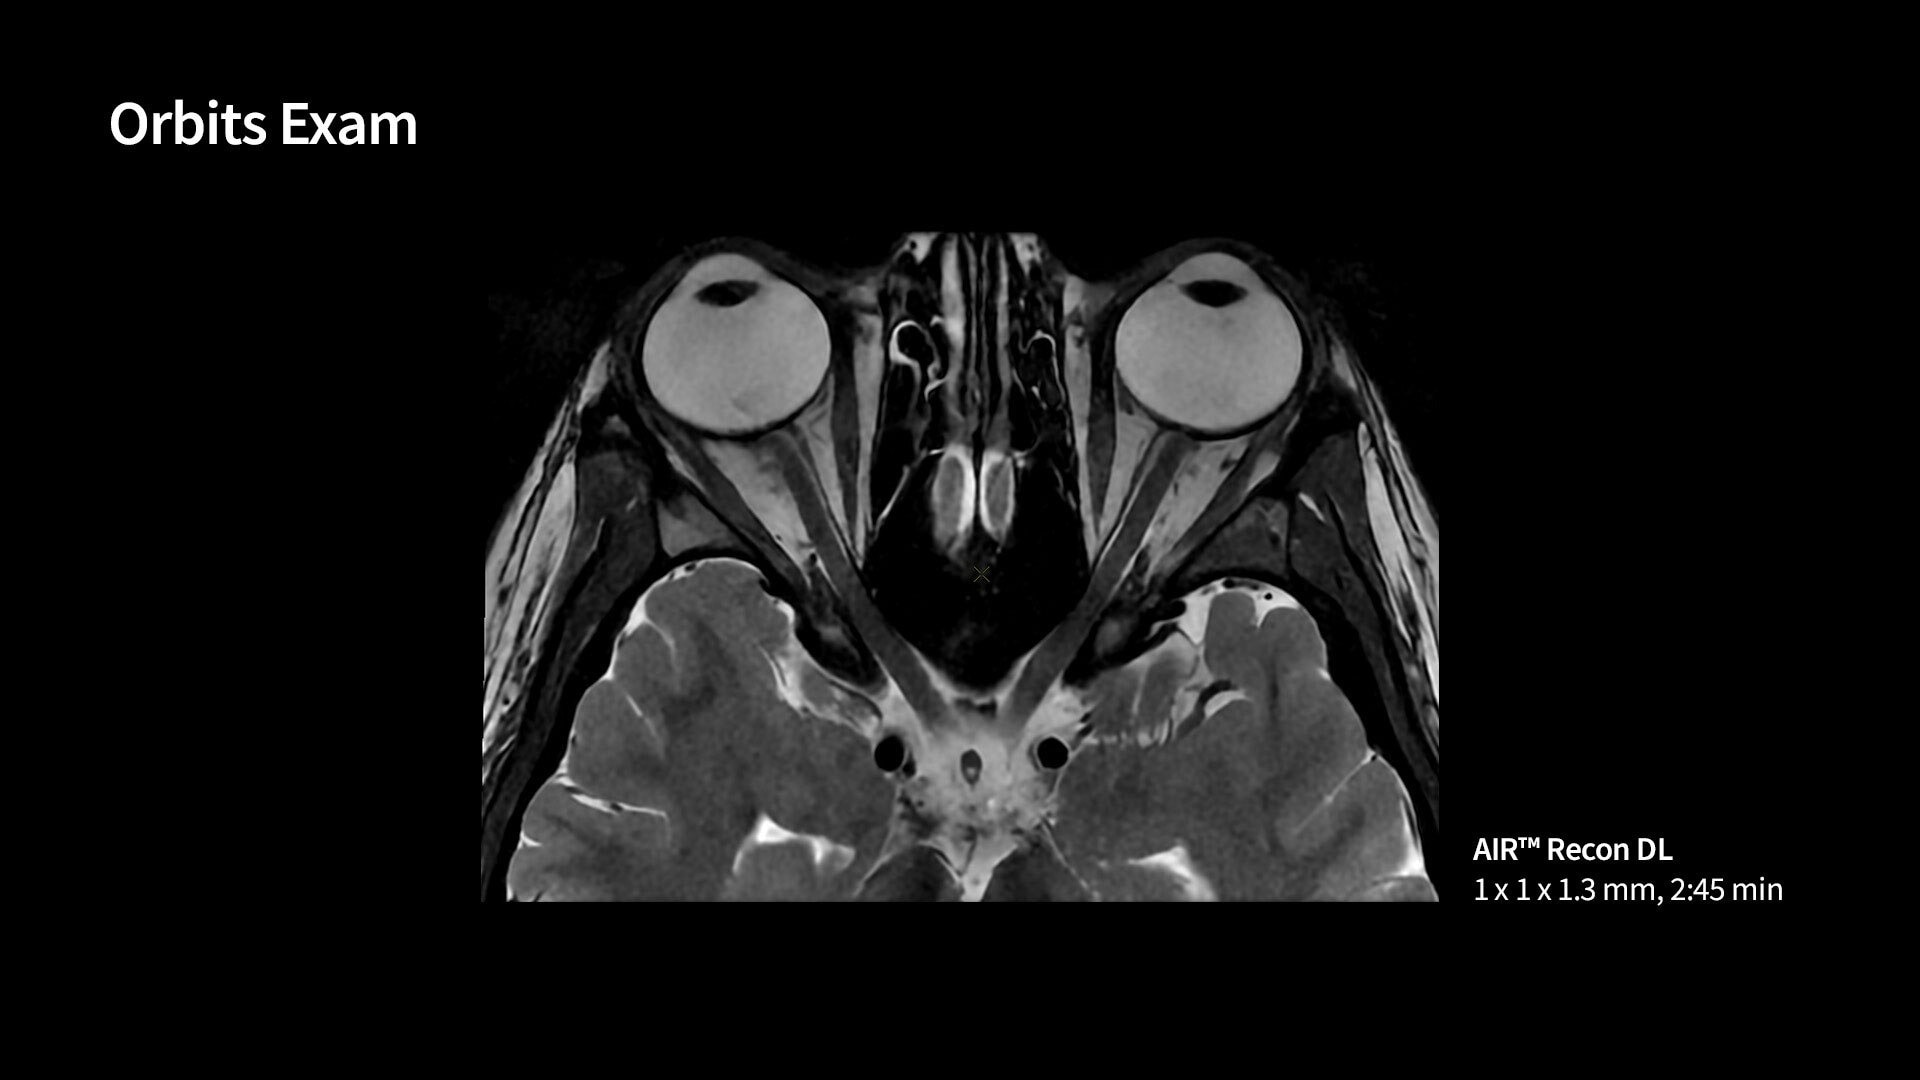

Neuro MRI for SIGNA

Wide range of MR neuro imaging techniques for fast images of brain, spine, vascular and peripheral nerve anatomy with exceptional tissue contrast.

Neurological MR imaging applications